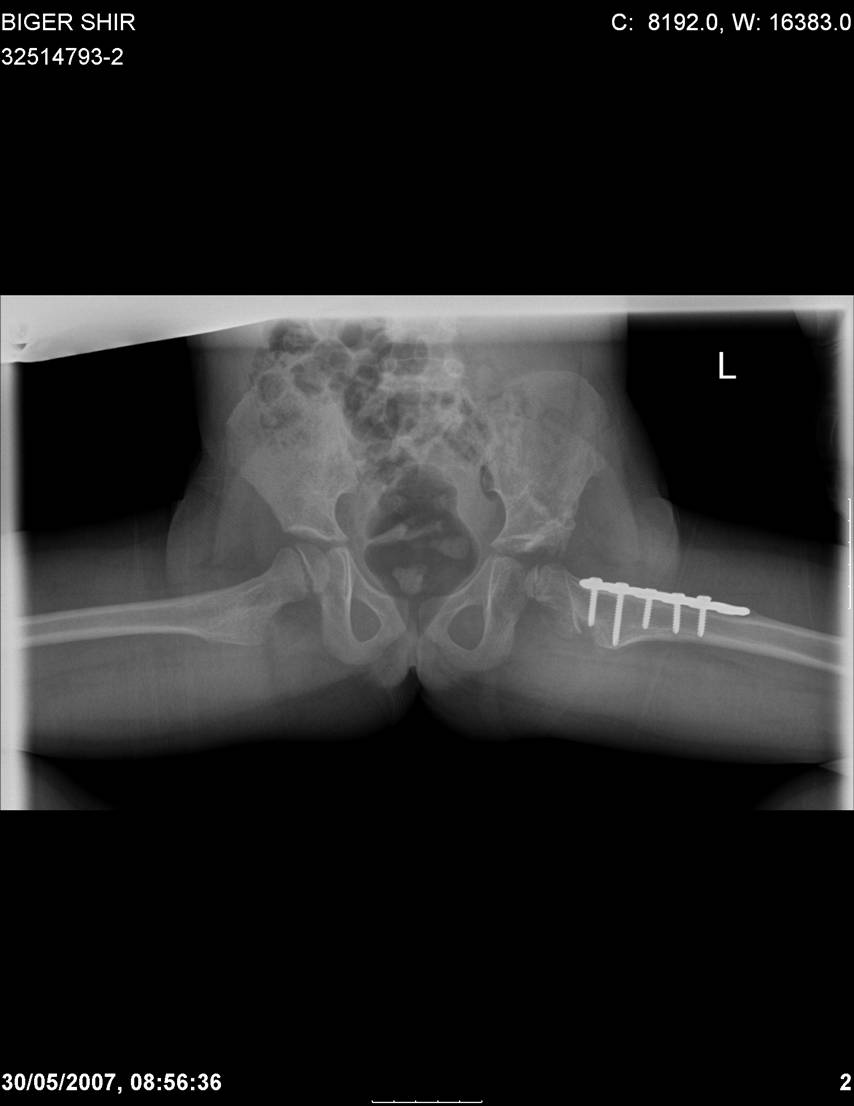

Navernoe Dega

Chto by ne byt goloslovnym posilau vam svoi sluchai gde sdelal vse chto napisal vyshe